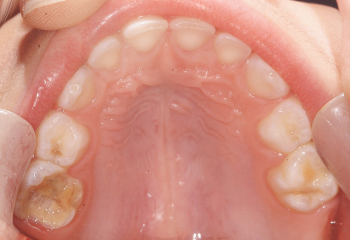

Odontopediatría

Caso 1